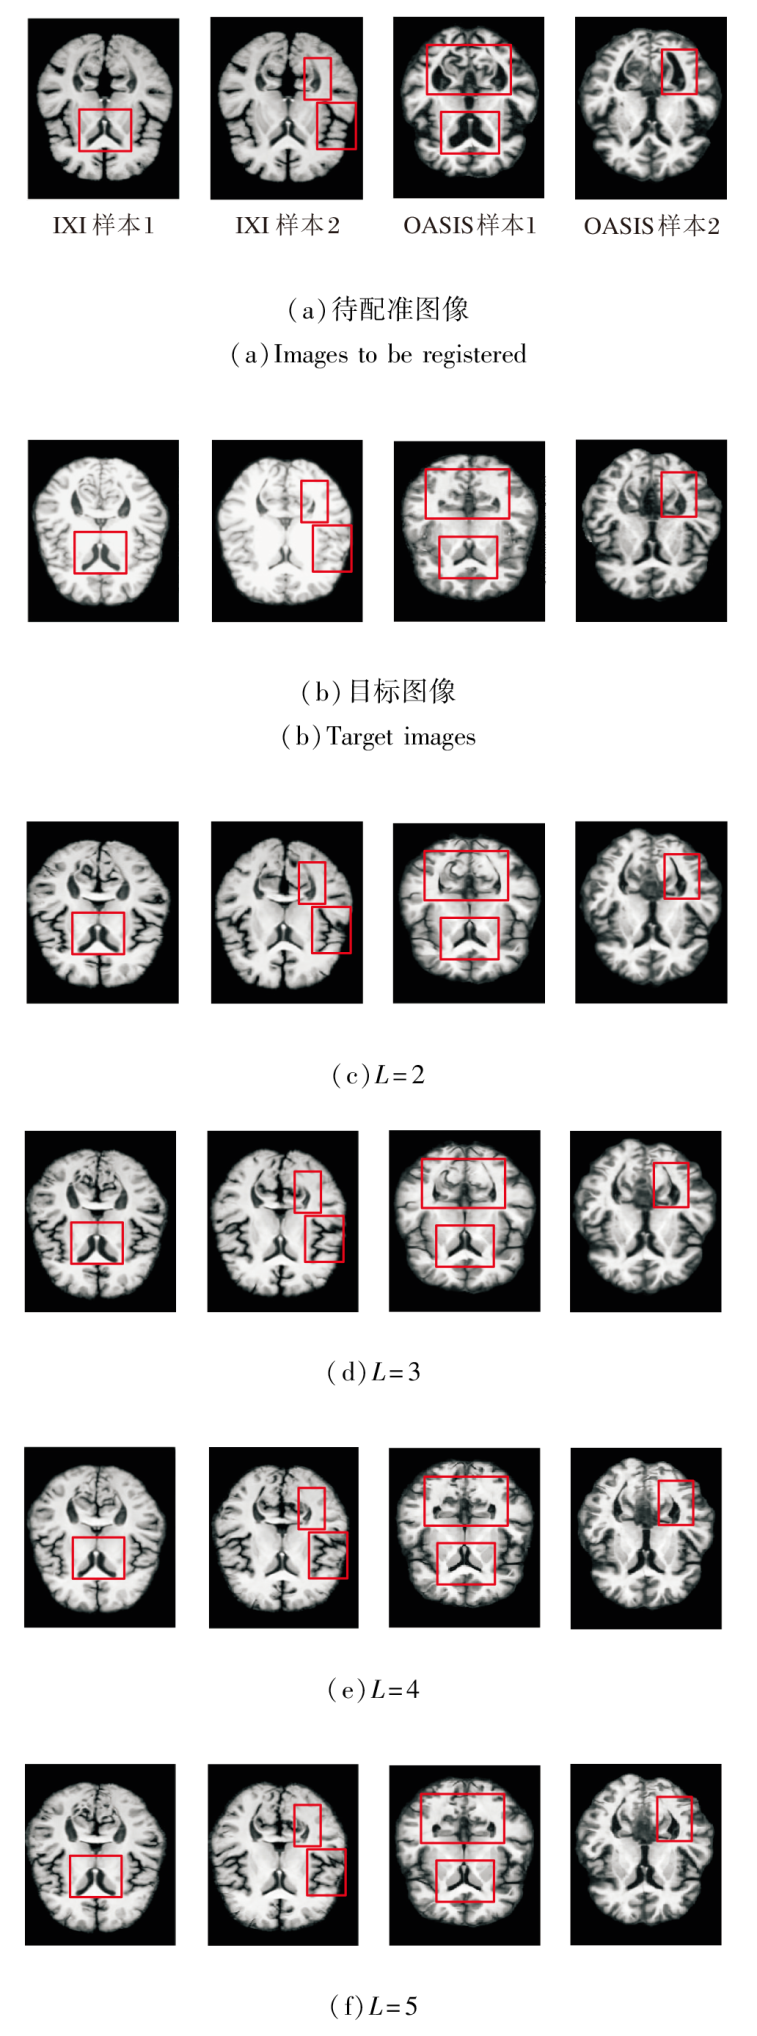

网络深度需在特征覆盖能力与计算效率之间取得平衡:层数过少可能难以捕捉跨尺度的形变特征, 而层数过多则会引入不必要的计算开销与过拟合风险.

为此, PyraMLP-Net采用4个编码层与4个解码层构成的四级金字塔结构, 实现由粗到精的渐进式配准.为了验证该层级设计的有效性, 以网络层级数L=4为基准, 对比L=2, 3, 5时的性能表现.

在IXI、OASIS数据集上各选取2个样本, 当网络层级数L改变时, 得到的图像配准结果如图11所示.L对PyraMLP-Net性能的影响如图12和表8所示.

由图11、图12和表8可见, 当L=2时, 网络深度不足, 导致多尺度特征提取不充分, 对细微解剖结构的匹配能力有限, 配准精度最低.L=3时, PyraMLP-Net能捕获更多的中等尺度特征, 性能优于两层网络, 但仍难以建模高分辨率细节.L=4时, PyraMLP-Net实现从低分辨率到全分辨率的完整特征覆盖, 能更精准地匹配解剖结构, 各项指标值均显著优于浅层结构.当L=5时, 其性能与4层网络相比未出现明显提升, 但计算开销显著增加.以IXI数据集为例, 单次运行时间从0.355 s增至0.418 s, 内存占用从14.823 GB升至16.018 GB.这表明对于具有典型分布和结构规律的脑部MRI数据, 4层网络已能充分学习其特征表示, 继续增加层数不仅无法带来性能增益, 反而会引入冗余参数并降低计算效率.

综合配准性能与资源效率, L=4能在满足精细解剖结构匹配要求的同时, 避免因层级不足或过度而导致的性能损失或计算资源浪费, 实现最佳平衡, 从而验证PyraMLP-Net四层架构的合理性.